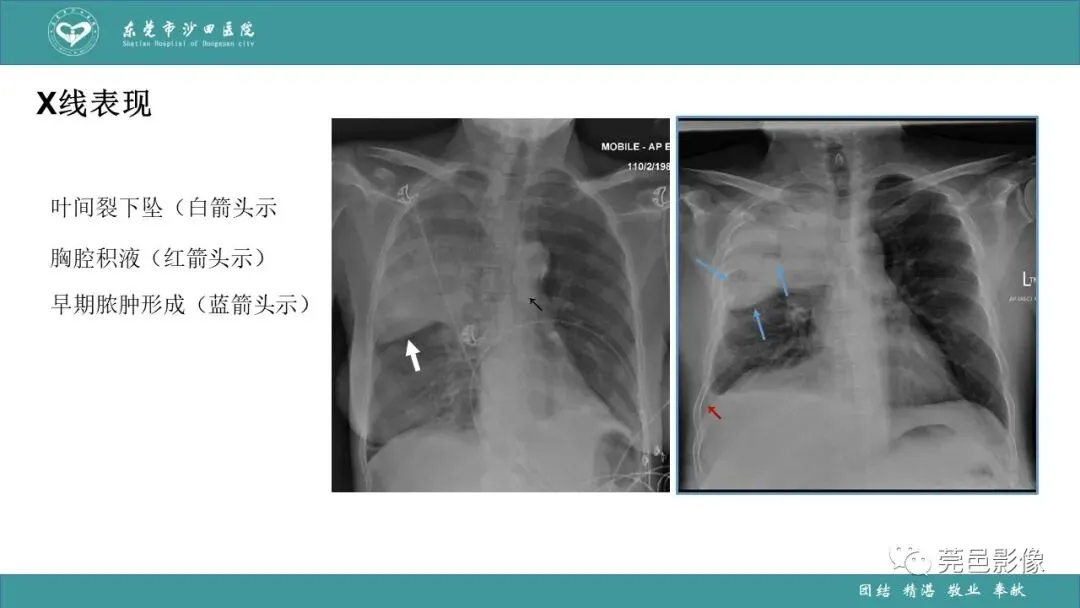

>课件 | 肺炎克雷伯杆菌肺炎影像学诊断与鉴别诊断

课件 | 肺炎克雷伯杆菌肺炎影像学诊断与鉴别诊断